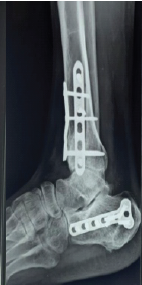

Management of Ipsilateral Pilon with Calcaneal Fractures: A Rare Case Report

Siddhart Yadav , K P Chiranjeevi , Akash Singh Jadon , Dharm Bedwal , Sameer Pandey

………………………………p.102-106